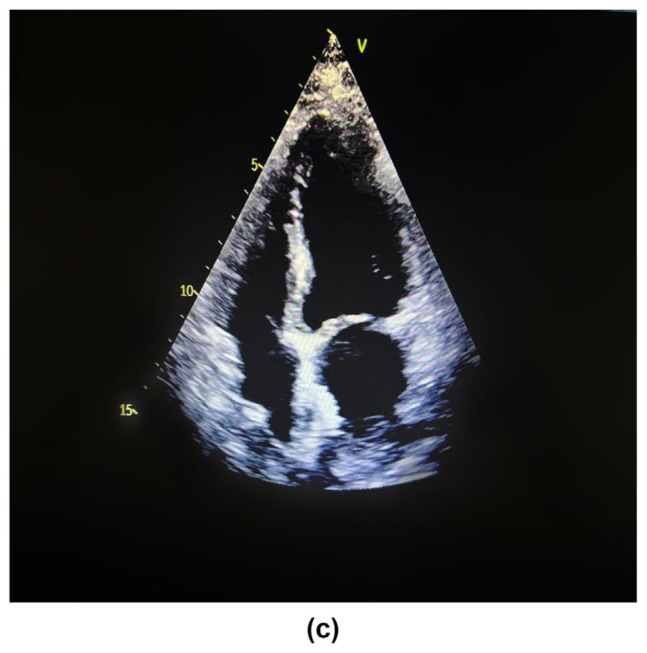

Spontaneous interatrial hematoma is a rare clinical entity leading to the obliteration of the left atrial cavity and causing haemodynamic compromise, necessitating immediate surgical intervention. Herein, we report a patient with acute chest pain with normal coronaries and echocardiographic evidence of left atrial mass. The investigations revealed the mass to be a thrombus rather than tumour. The patient underwent surgery to remove a large thrombus completely enclosed within the interatrial septum. The septum was then repaired using a pericardial patch. No apparent etiological factor was found. Spontaneous atrial wall dissection should be considered in the differential diagnosis of acute chest pain.